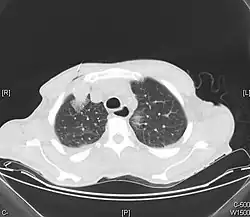

40–60% guzów nerek jest rozpoznawanych przypadkowo podczas badania wykonanego z innego powodu niż podejrzenie raka nerki. Większość guzów nerek może być rozpoznana za pomocą badań obrazowych. Najważniejszym kryterium diagnostycznym jest obecność wzmocnienia sygnału. W diagnostyce największe znaczenie mają: tomografia komputerowa, rezonans magnetyczny oraz USG z kontrastem[60].

Tomografia komputerowa jest podstawową metodą oceny stopnia zaawansowania guza nerki. W TK wzmocnienie kontrastowe jest oceniane za pomocą porównania obrazu zmiany przed i po podaniu kontrastu. Wzmocnienie sygnału >20 j.H. (jednostek Hounsfielda) wskazuje na wzmocnienie kontrastowe, które przemawia za obrazem guza nerki[2][61][62][63][64].